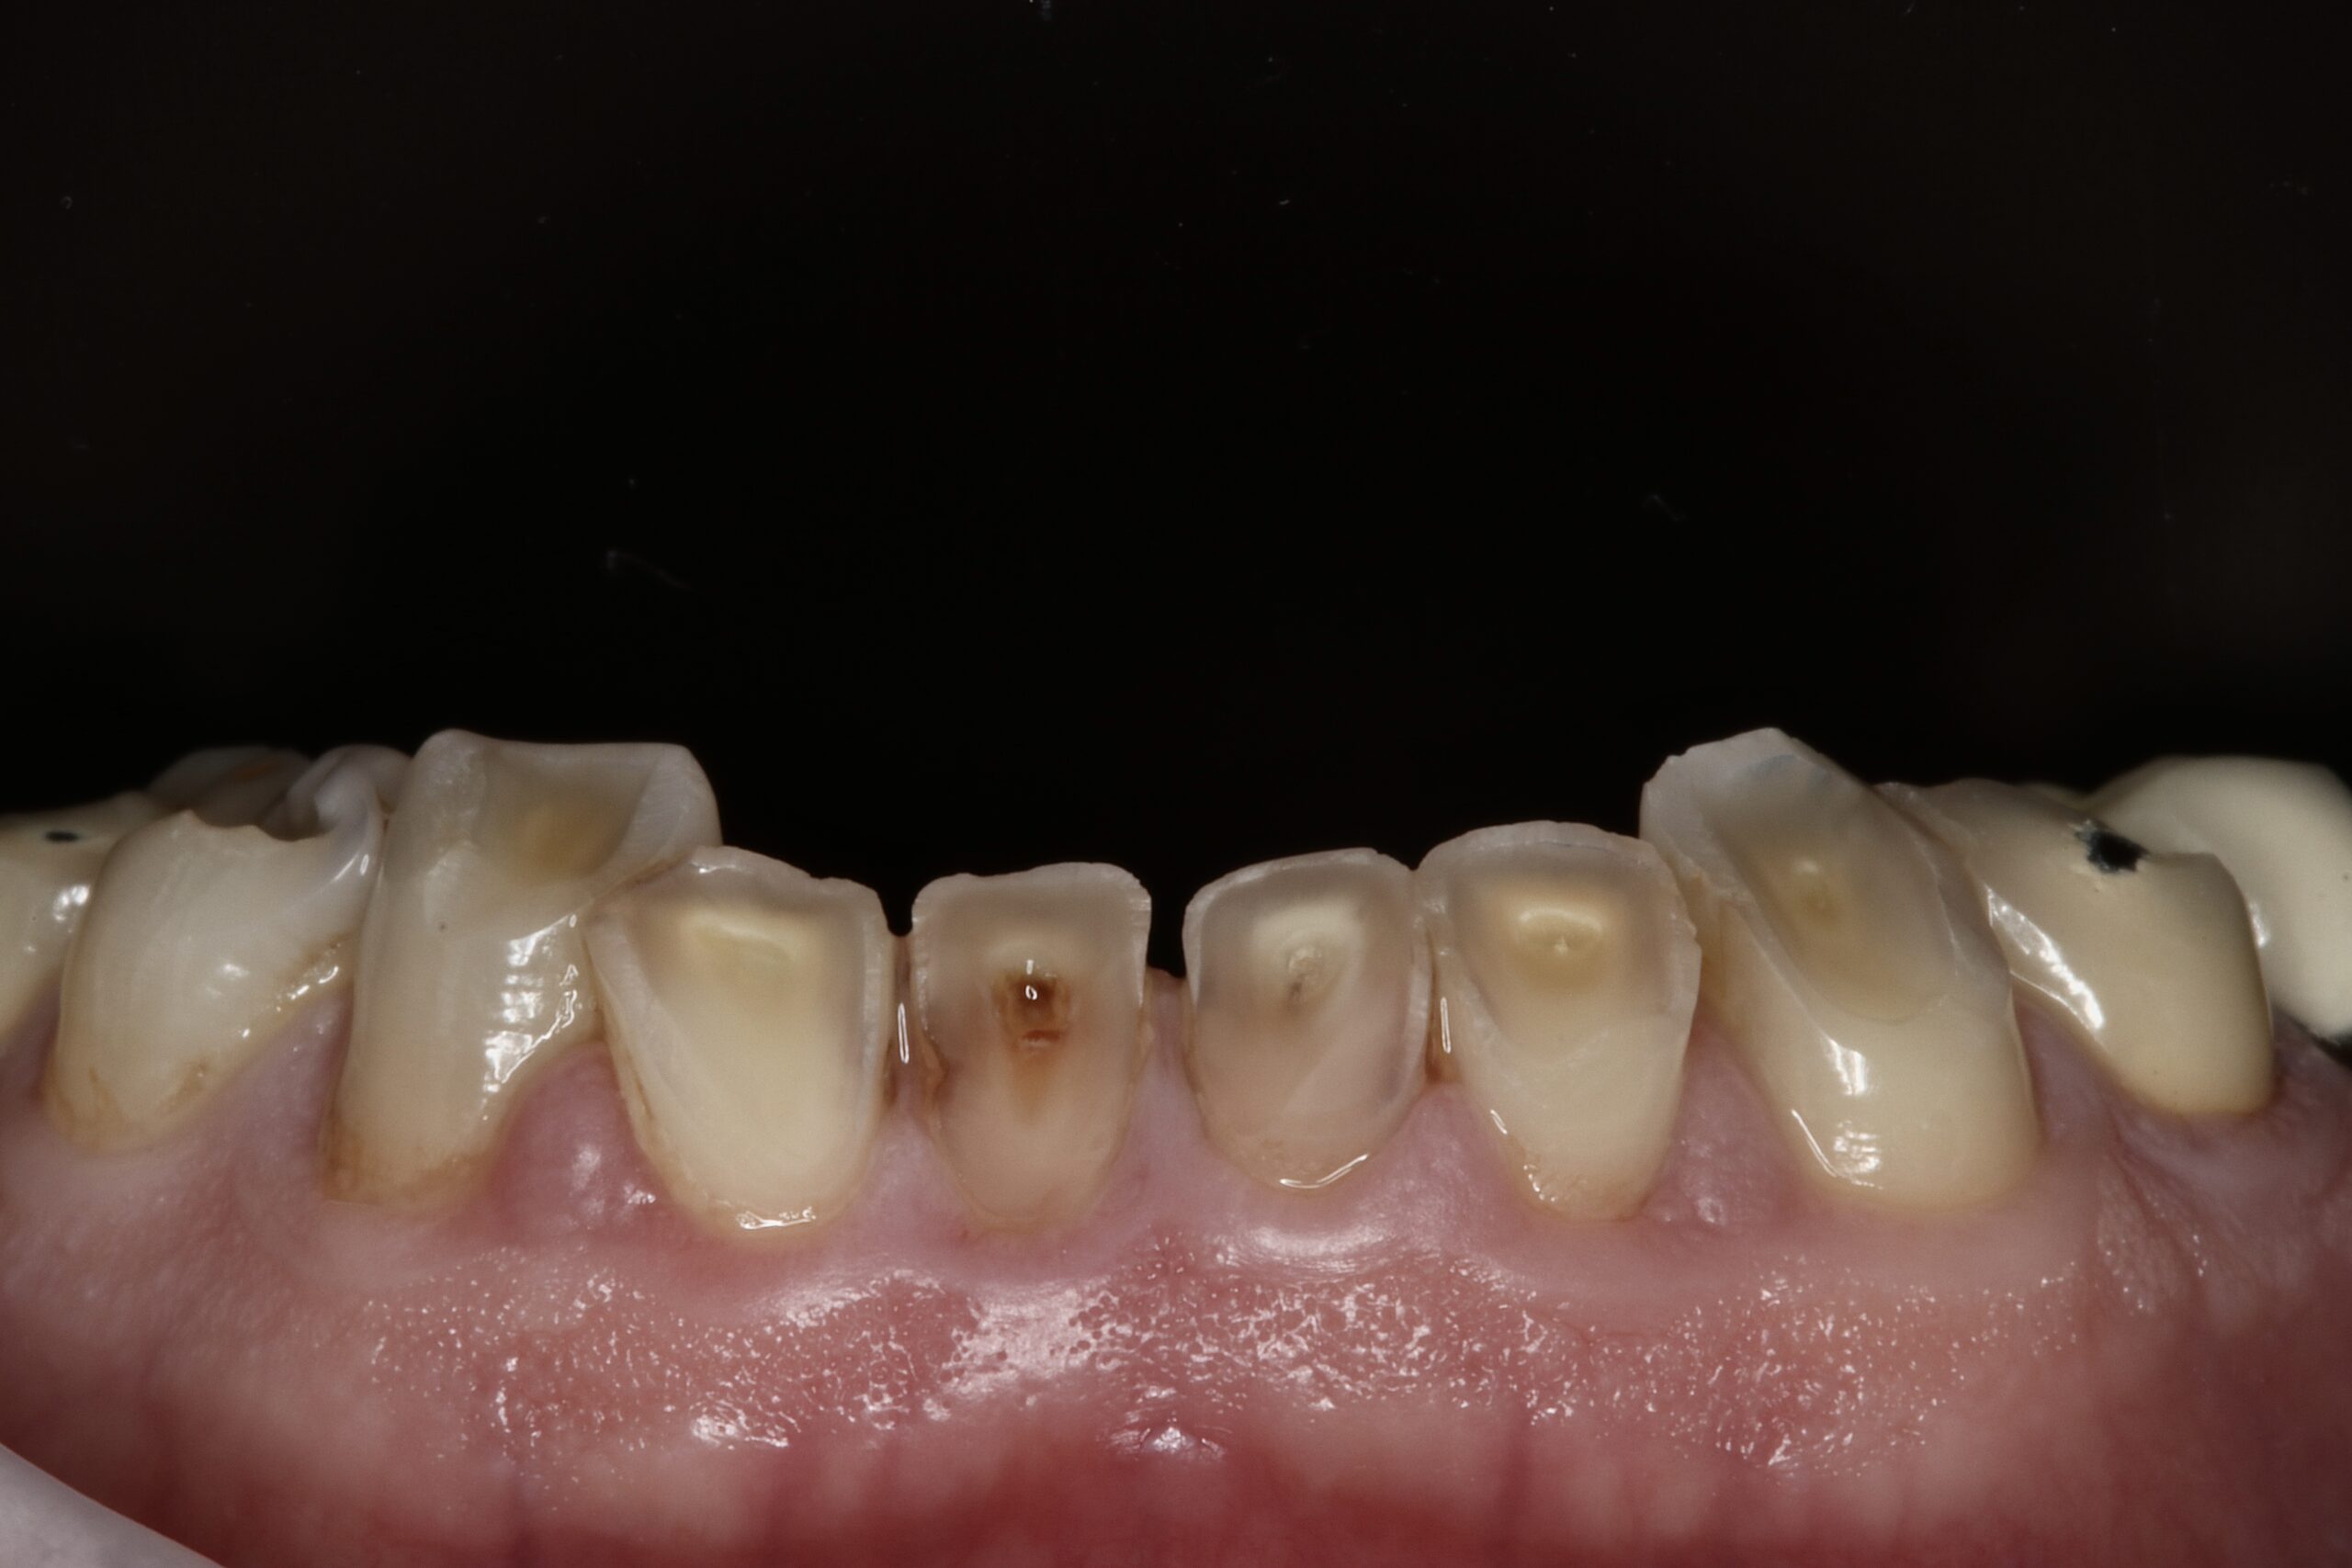

Cas 3

Dr Eyal Assaraf Réhabilitation d’un cas d’érosion dentaire